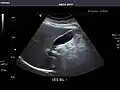

Abdominal Ultrasound (Full Exam)

STRUCTURED REPORT

(Technique: Transabdominal ultrasonography; Device: Toshiba Aplio XG)

Kidneys: Right and left kidneys measure 11.5 cm and 12 cm in length respectively. No hydronephrosis. Small left lower pole kidney cyst.

Ascites: None.

Aorta: Visualized portions normal in caliber, 16 x 15 mm.

IVC: Normal.

IMPRESSION:

Normal abdominal ultrasound.

Left kidney -